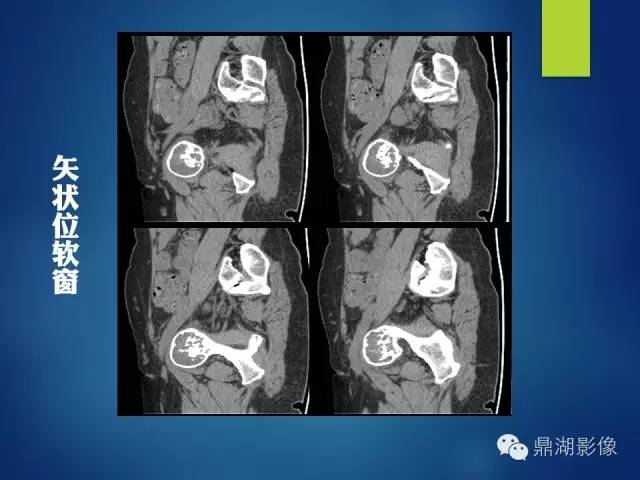

影像表现:

左侧耻骨可见一不规则略低于软组织密度影,周围骨皮质变薄,其内可见丝瓜囊样密度增高影,未见明显骨膜反应及骨折线。